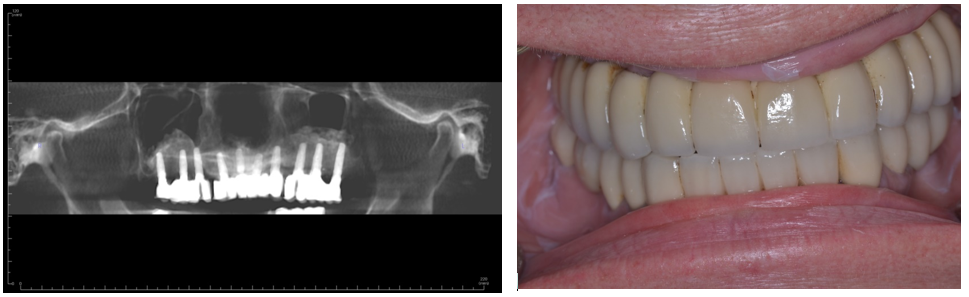

Figure 4 (a & b). Six-year follow-up demonstrating final prosthesis with three independent bridges. Good bone support has been maintained around the implants with only mild bone loss around one implant with signs inflammation. Our current philosophy would place only three to four implants per side avoiding implants in the incisor area.